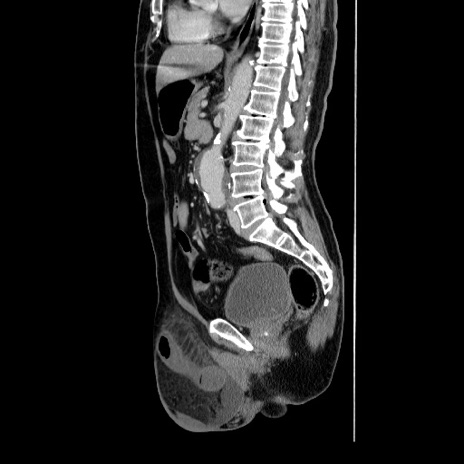

症例34(矢状断像)

【症例】60歳代 男性

【主訴】右鼠径部膨隆

【現病歴】1年程前より右鼠径部膨隆あり。自己にて還納可能だったため放置していた。3時間前より右鼠径部の脱出を認め、還納困難となり受診。

【身体所見】右鼠径部に小児頭大の膨隆あり。弾性硬であり、用手還納は困難。左鼠径部にも膨隆を認める。脱出はなし。